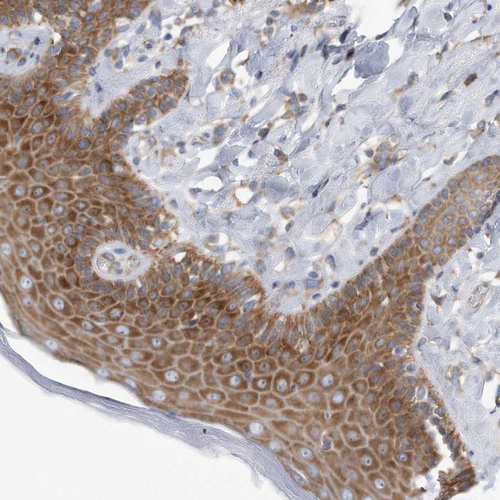

Immunohistochemical staining of human pancreas shows strong cytoplasmic positivity in exocrine glandular cells.